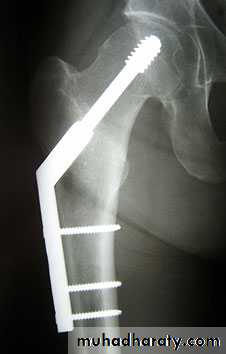

4.DHS.

1.Sliding nail

2.L-plate